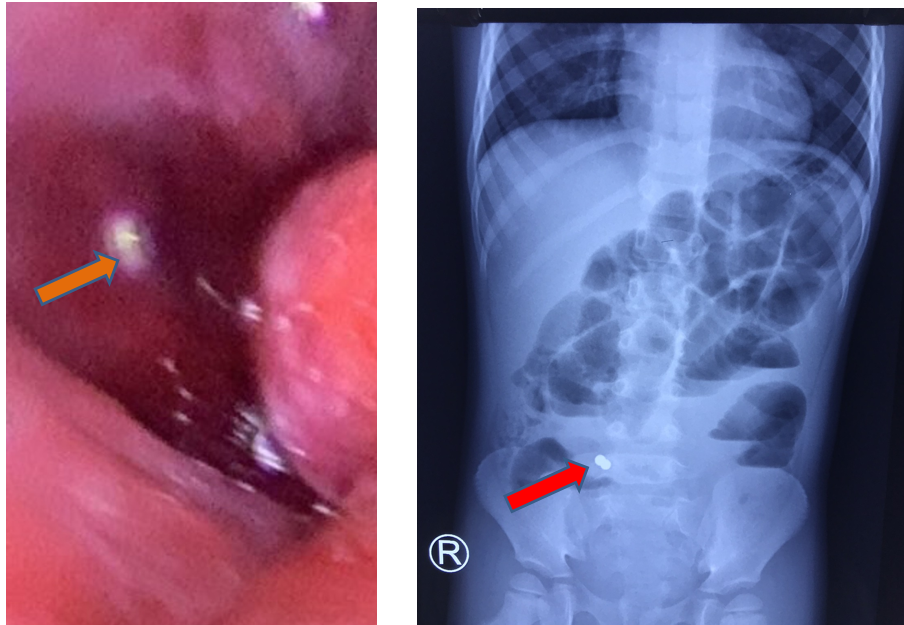

| Dị vật được xác định là các viên bi nam châm (ảnh: BVCC) |

Tại đây trẻ được các bác sĩ thăm khám, xét nghiệm, chẩn đoán hình ảnh X-quang bụng đứng không sữa soạn cho thấy có hình ảnh mực nước hơi kèm dị vật kim loại theo dõi pin hoặc nam châm, nên được hội chẩn bác sĩ ngoại khoa chuyển phòng mổ tiến hành phẫu thuật nội soi ghi nhận các quai hỗng tràng dãn, thành dày.